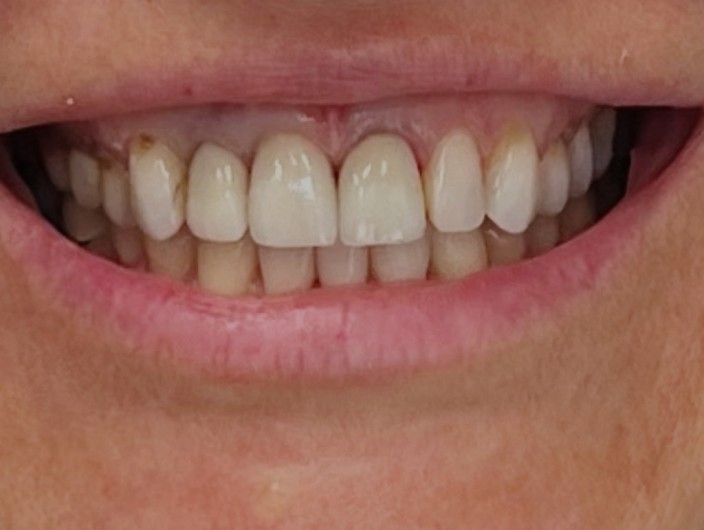

Poprawa estetyki uśmiechu: wybielanie zębów.

Profilaktyka i estetyka: usuwanie kamienia i wybielanie.